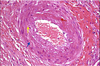

What atheroscleortic complication is this?

Fixed vessel narrowing (coronary artery)

Red circle denotes normal lumen size

H&E: fibrous placque (not as much lipid as L)